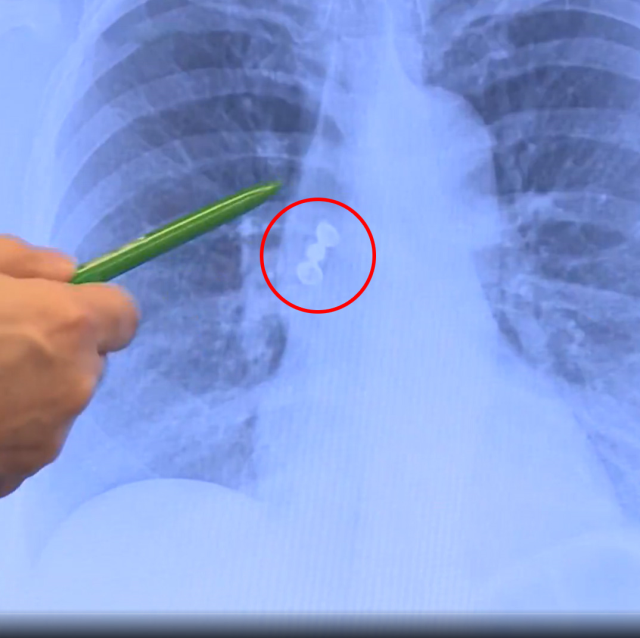

Hastanede çekilen akciğer grafisi, olayın seyrini değiştirdi. Üç dişten oluşan kaplama köprünün akciğere kaçtığı belirlendi. Doktorlar, solunum yollarını tıkama riski bulunan durum nedeniyle hastayı hemen tedavi altına aldı. Kaplama diş, bronkoskopi yöntemiyle başarılı şekilde çıkarıldı.

TRT Haber'e konuşan Göğüs Hastalıkları Uzmanı Prof. Dr. Levent Alpay, akciğer filminde kaplama köprünün aspire edildiğini tespit ettiklerini ve hastayı hemen yatırdıklarını söyledi. Alpay, bu tür vakaların genellikle çocuklarda görüldüğünü, erişkinlerde ise oldukça nadir rastlandığını belirtti.